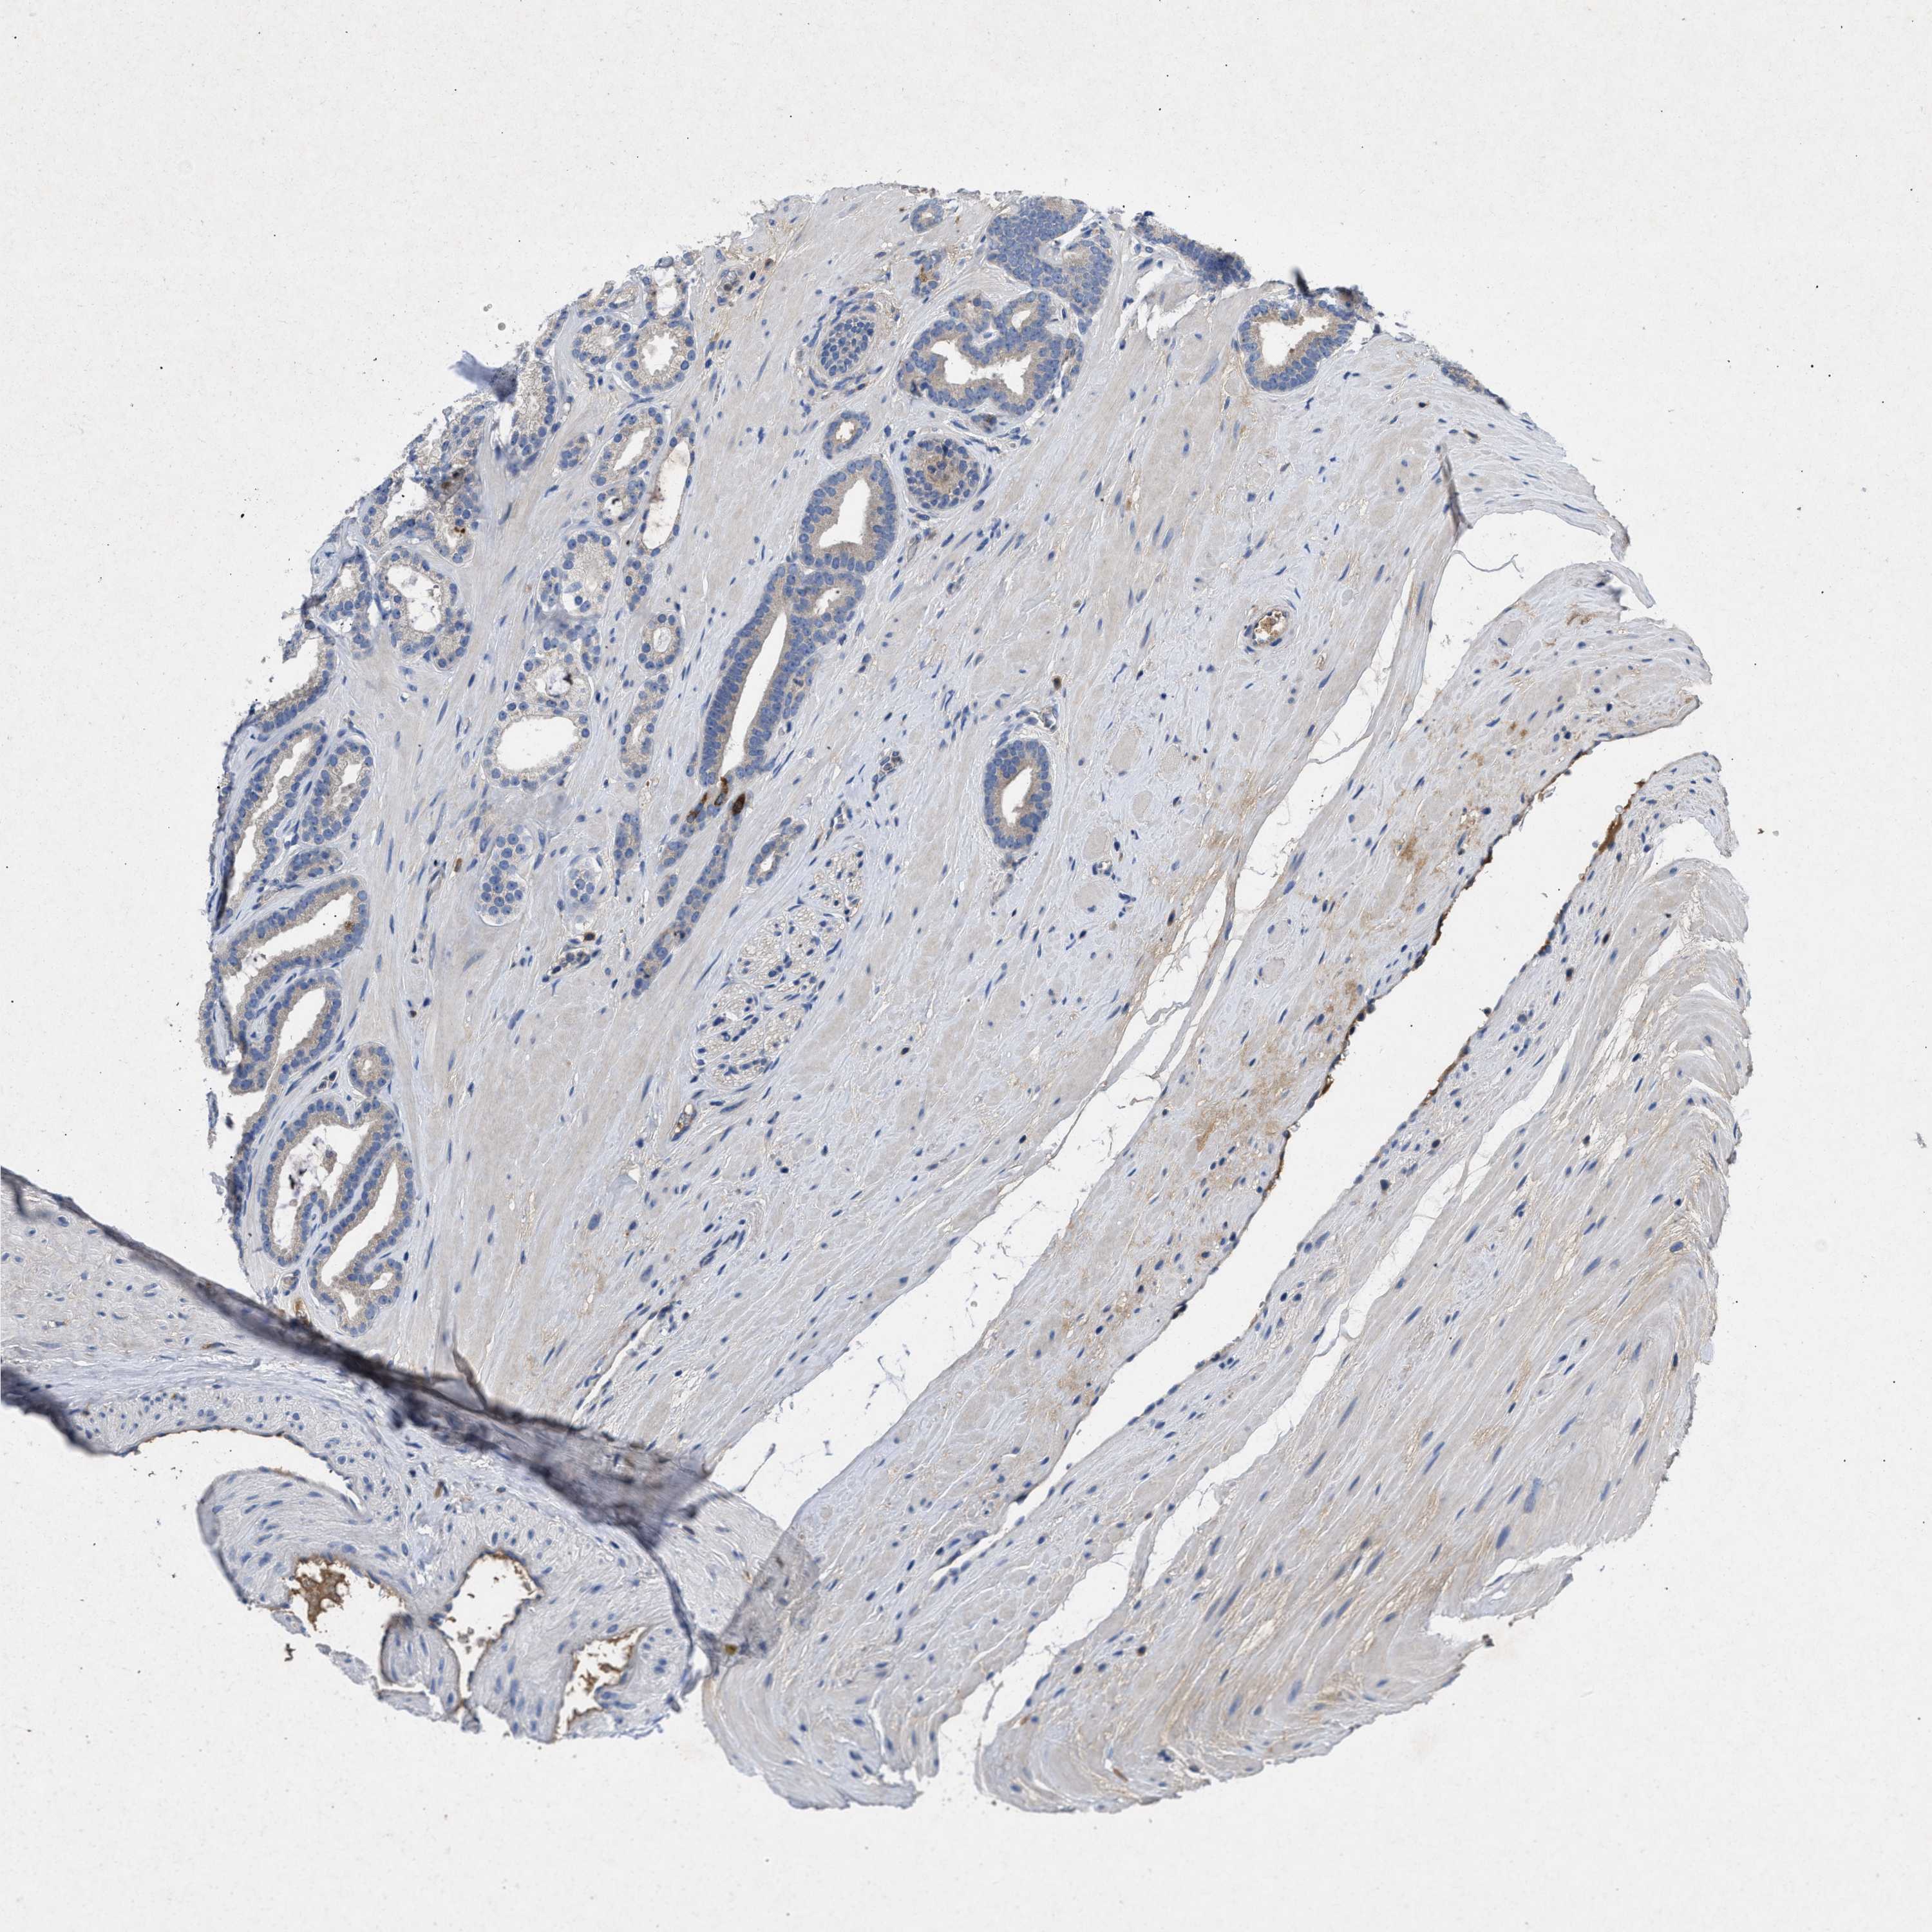

PROSTATE CANCER - Protein expressioni

A mouse-over function shows sample information and annotation data. Click on an image to view it in a full screen mode. Samples can be filtered based on level of antibody staining by selecting one or several of the following categories: high, medium, low and not detected. The assay and annotation is described here.

Note that samples used for immunohistochemistry by the Human Protein Atlas do not correspond to samples in the TCGA dataset.

Antibody stainingi

Antibody staining in the annotated cell types in the current human tissue is reported as not detected, low, medium, or high, based on conventional immunohistochemistry profiling in selected tissues. This score is based on the combination of the staining intensity and fraction of stained cells.

Each image is clickable and will lead to virtual microscopy that enables deeper exploration of all samples and also displays staining intensity scores, fraction scores and subcellular localization as well as patient and tissue information for each sample.

Antibody CAB018751

Antibody CAB034411

Staining

High

Medium

Low

Not detected

Intensity

Strong

Moderate

Weak

Negative

Quantity

>75%

75%-25%

<25%

None

Location

Nuclear

Cytoplasmic/membranous

Cytoplasmic/membranous,nuclear

Adenocarcinoma, High grade

Adenocarcinoma, Low grade